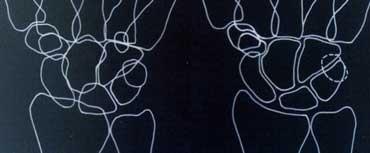

Bước tiếp theo là quan sát ba cung cổ tay: các đường cong trơn nối liền các bề mặt của các xương cổ tay như được minh họa ở hình bên trái.

Cung thứ nhất là một đường cong trơn phác thảo các mặt lồi phía gần của xương thuyền, xương nguyệt và xương tháp.

Cung thứ hai đi theo các bề mặt lõm phía xa của các xương tương tự, và cung thứ ba đi theo các đường cong phía gần chính của xương đầu và xương móc.

Phim X-quang cổ tay tư thế thẳng (PA) và hình minh họa sơ đồ cho thấy sự gián đoạn của cung cổ tay thứ nhất

Gián đoạn các cung cổ tay

Một cung được coi là gián đoạn khi không thể vẽ theo một đường cong trơn liên tục. Sự gián đoạn của một trong các cung cho thấy có gãy xương hoặc đứt dây chằng dẫn đến bán trật khớp hoặc trật khớp.

Ở hình bên trái, có thể nhận thấy sự gián đoạn của cung I tại khớp nguyệt-tháp.

Hình bên trái cho thấy sự gián đoạn của cung cổ tay thứ hai tại khớp thuyền-nguyệt và khớp nguyệt-tháp. Mặc dù có một khoảng hở ở cung thứ nhất, nhưng vẫn có thể vẽ theo một đường cong trơn liên tục, do đó cung I được coi là còn nguyên vẹn.

Sự gián đoạn của cung cổ tay thứ ba được minh họa trong trường hợp tiếp theo ở hình bên trái. Có hiện tượng bậc thang bất thường tại khớp đầu-móc.